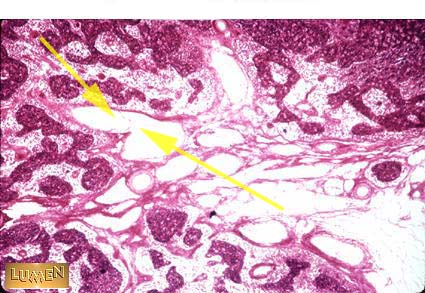

What vessel is this?

Answer

Efferent Lymphatics